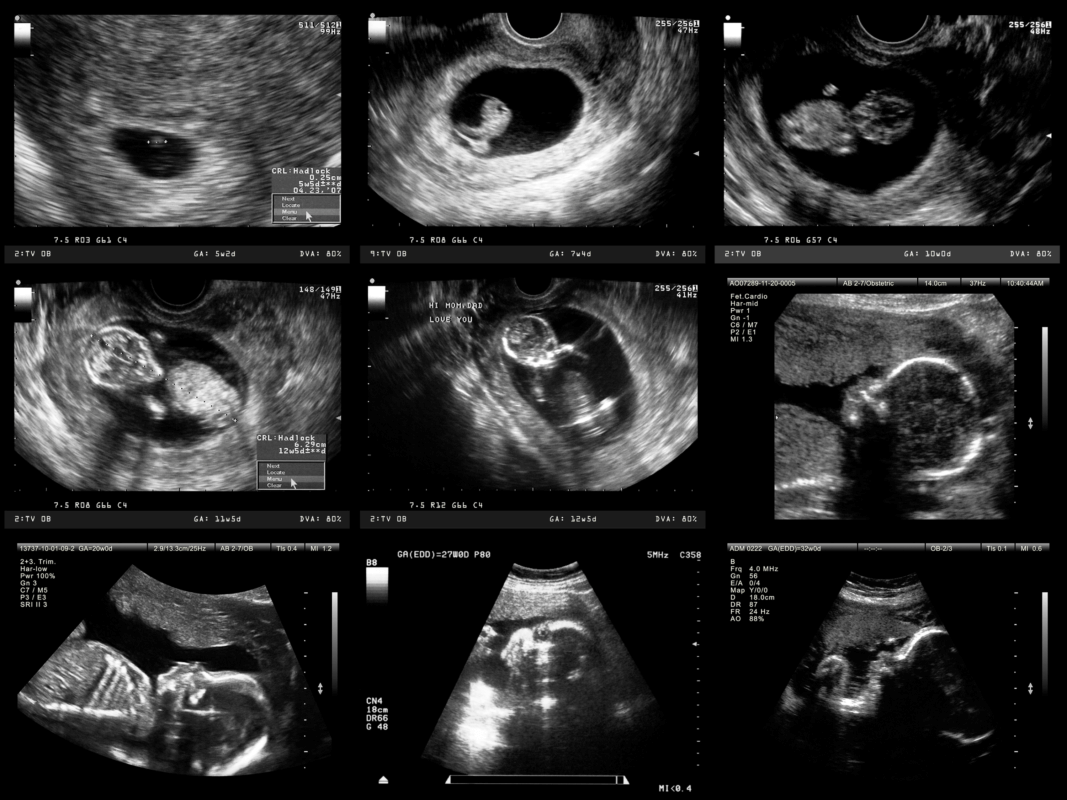

Ultraschall: So kannst Du die Entwicklung Deines Babys beobachten

Es ist normaler Bestandteil der Voruntersuchungen, regelmäßig einen Ultraschall zu machen. Die drei großen Ultraschalluntersuchungen können wichtige Hinweise auf den Entwicklungs- und Gesundheitszustandes Deines Babys liefern.

Und natürlich ist es total aufregend! Auch wenn Dein Baby noch nicht auf der Welt ist, kannst Du es schon früh beobachten und beim Wachsen zuschauen.

Der erste große Ultraschall:

- Theoretisch lässt sich schon ab der 5. SSW ein erstes kleines Pünktchen erkennen.

- Dein Frauenarzt oder Deine Frauenärztin wird vermutlich bis zur 9. SSW mit dem ersten Ultraschall warten. Ab hier kannst auch Du den Embryo schon richtig sehen.

- Es kann außerdem festgestellt werden, ob Du Zwillinge oder Mehrlinge erwartest.

- Besonders emotional finden viele werdende Mütter den Moment, in dem sie zum ersten Mal den Herzschlag ihres Kindes über den Ultraschall hören.

Der zweite große Ultraschall:

- Die zweite große Ultraschalluntersuchung wird wahrscheinlich zwischen der 19. und 22. SSW stattfinden.

- Hier ist der Embryo schon ordentlich herangewachsen und man kann häufig auch schon das Geschlecht erkennen.

Der dritte große Ultraschall:

- Zwischen der 29. und 32. SSW wird der letzte große Ultraschall gemacht.

- Der oder die Gynäkolog:in überprüft nochmals die Entwicklung des Babys und die Kindslage und die der Plazenta, was für die bevorstehende Geburt relevant ist.